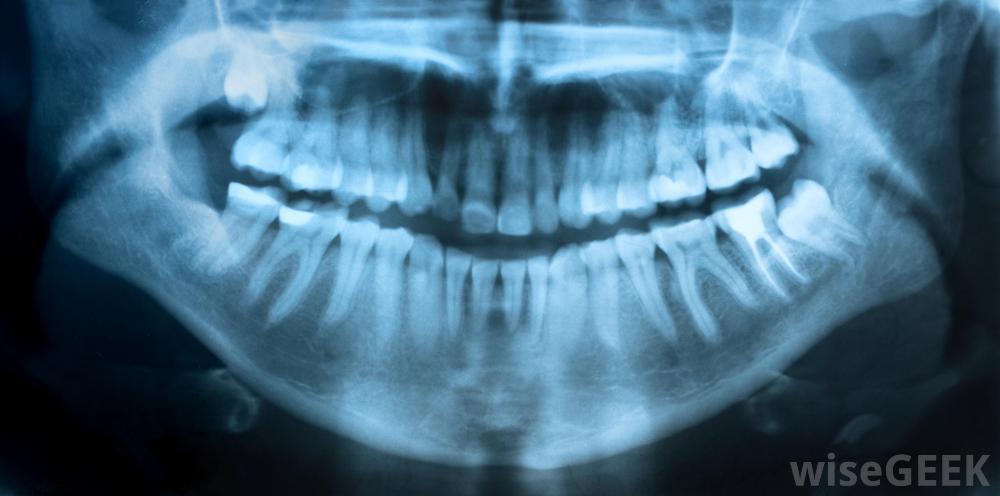

X光片是磨牙根管的組成部分。

磨牙根管可能需要幾個小時。對感染的牙齒進行X光檢查,以確定有多少根根管存在,以及在哪里進行治療。磨牙可以有兩到四根根根管,可能需要多次就診有些情況下,在磨牙根管手術之前、期間或之后,可能會使用抗生素。